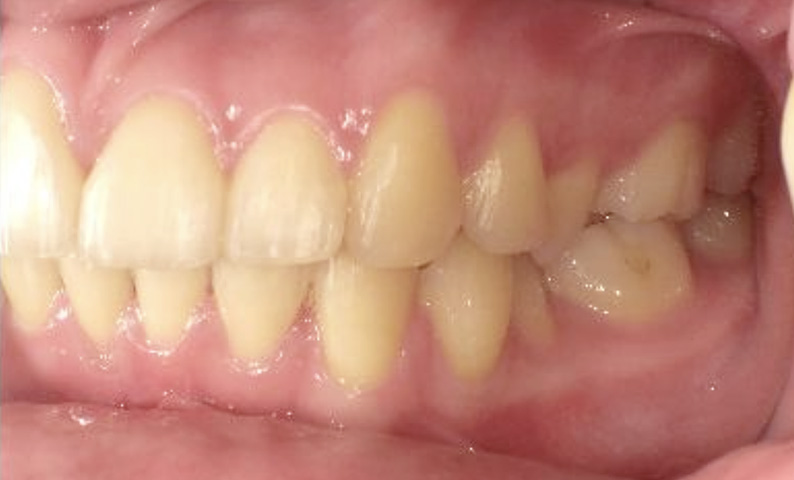

症例_024 上顎だけの部分矯正

治療期間:7ヶ月金額:30万円+税女性前歯のガタガタ上の前歯だけ